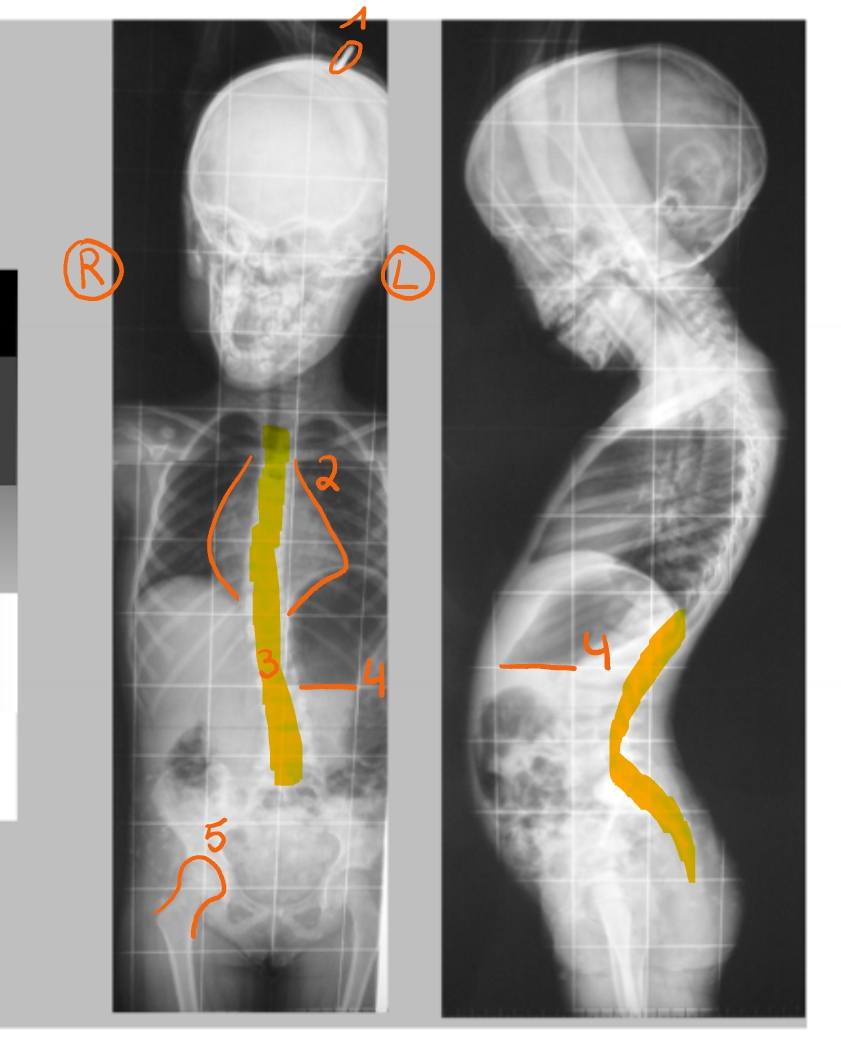

metaal

ring van de moeder die het hoofd vasthoudt

longen + ribben

in het midden: mediastinum

= structuren tussen de longen (bv. ook het hart)

wervelzuil

afwijking: verloopt in een boog (zijkant) = scoliose

afwijking: rugspieren niet al te sterk = hyperlordose

maag

boven horizontale lijn: gas (zwart)

onder horizontale lijn: vocht (grijs)

rechterheup

femurfractuur → intramedullaire nagel in het been (metaal)

Hoe foto bekijken?

‘you face the patient’

je kijkt naar de patient

patient kijkt naar jou

vorm van het hart

luchtbel in de maag